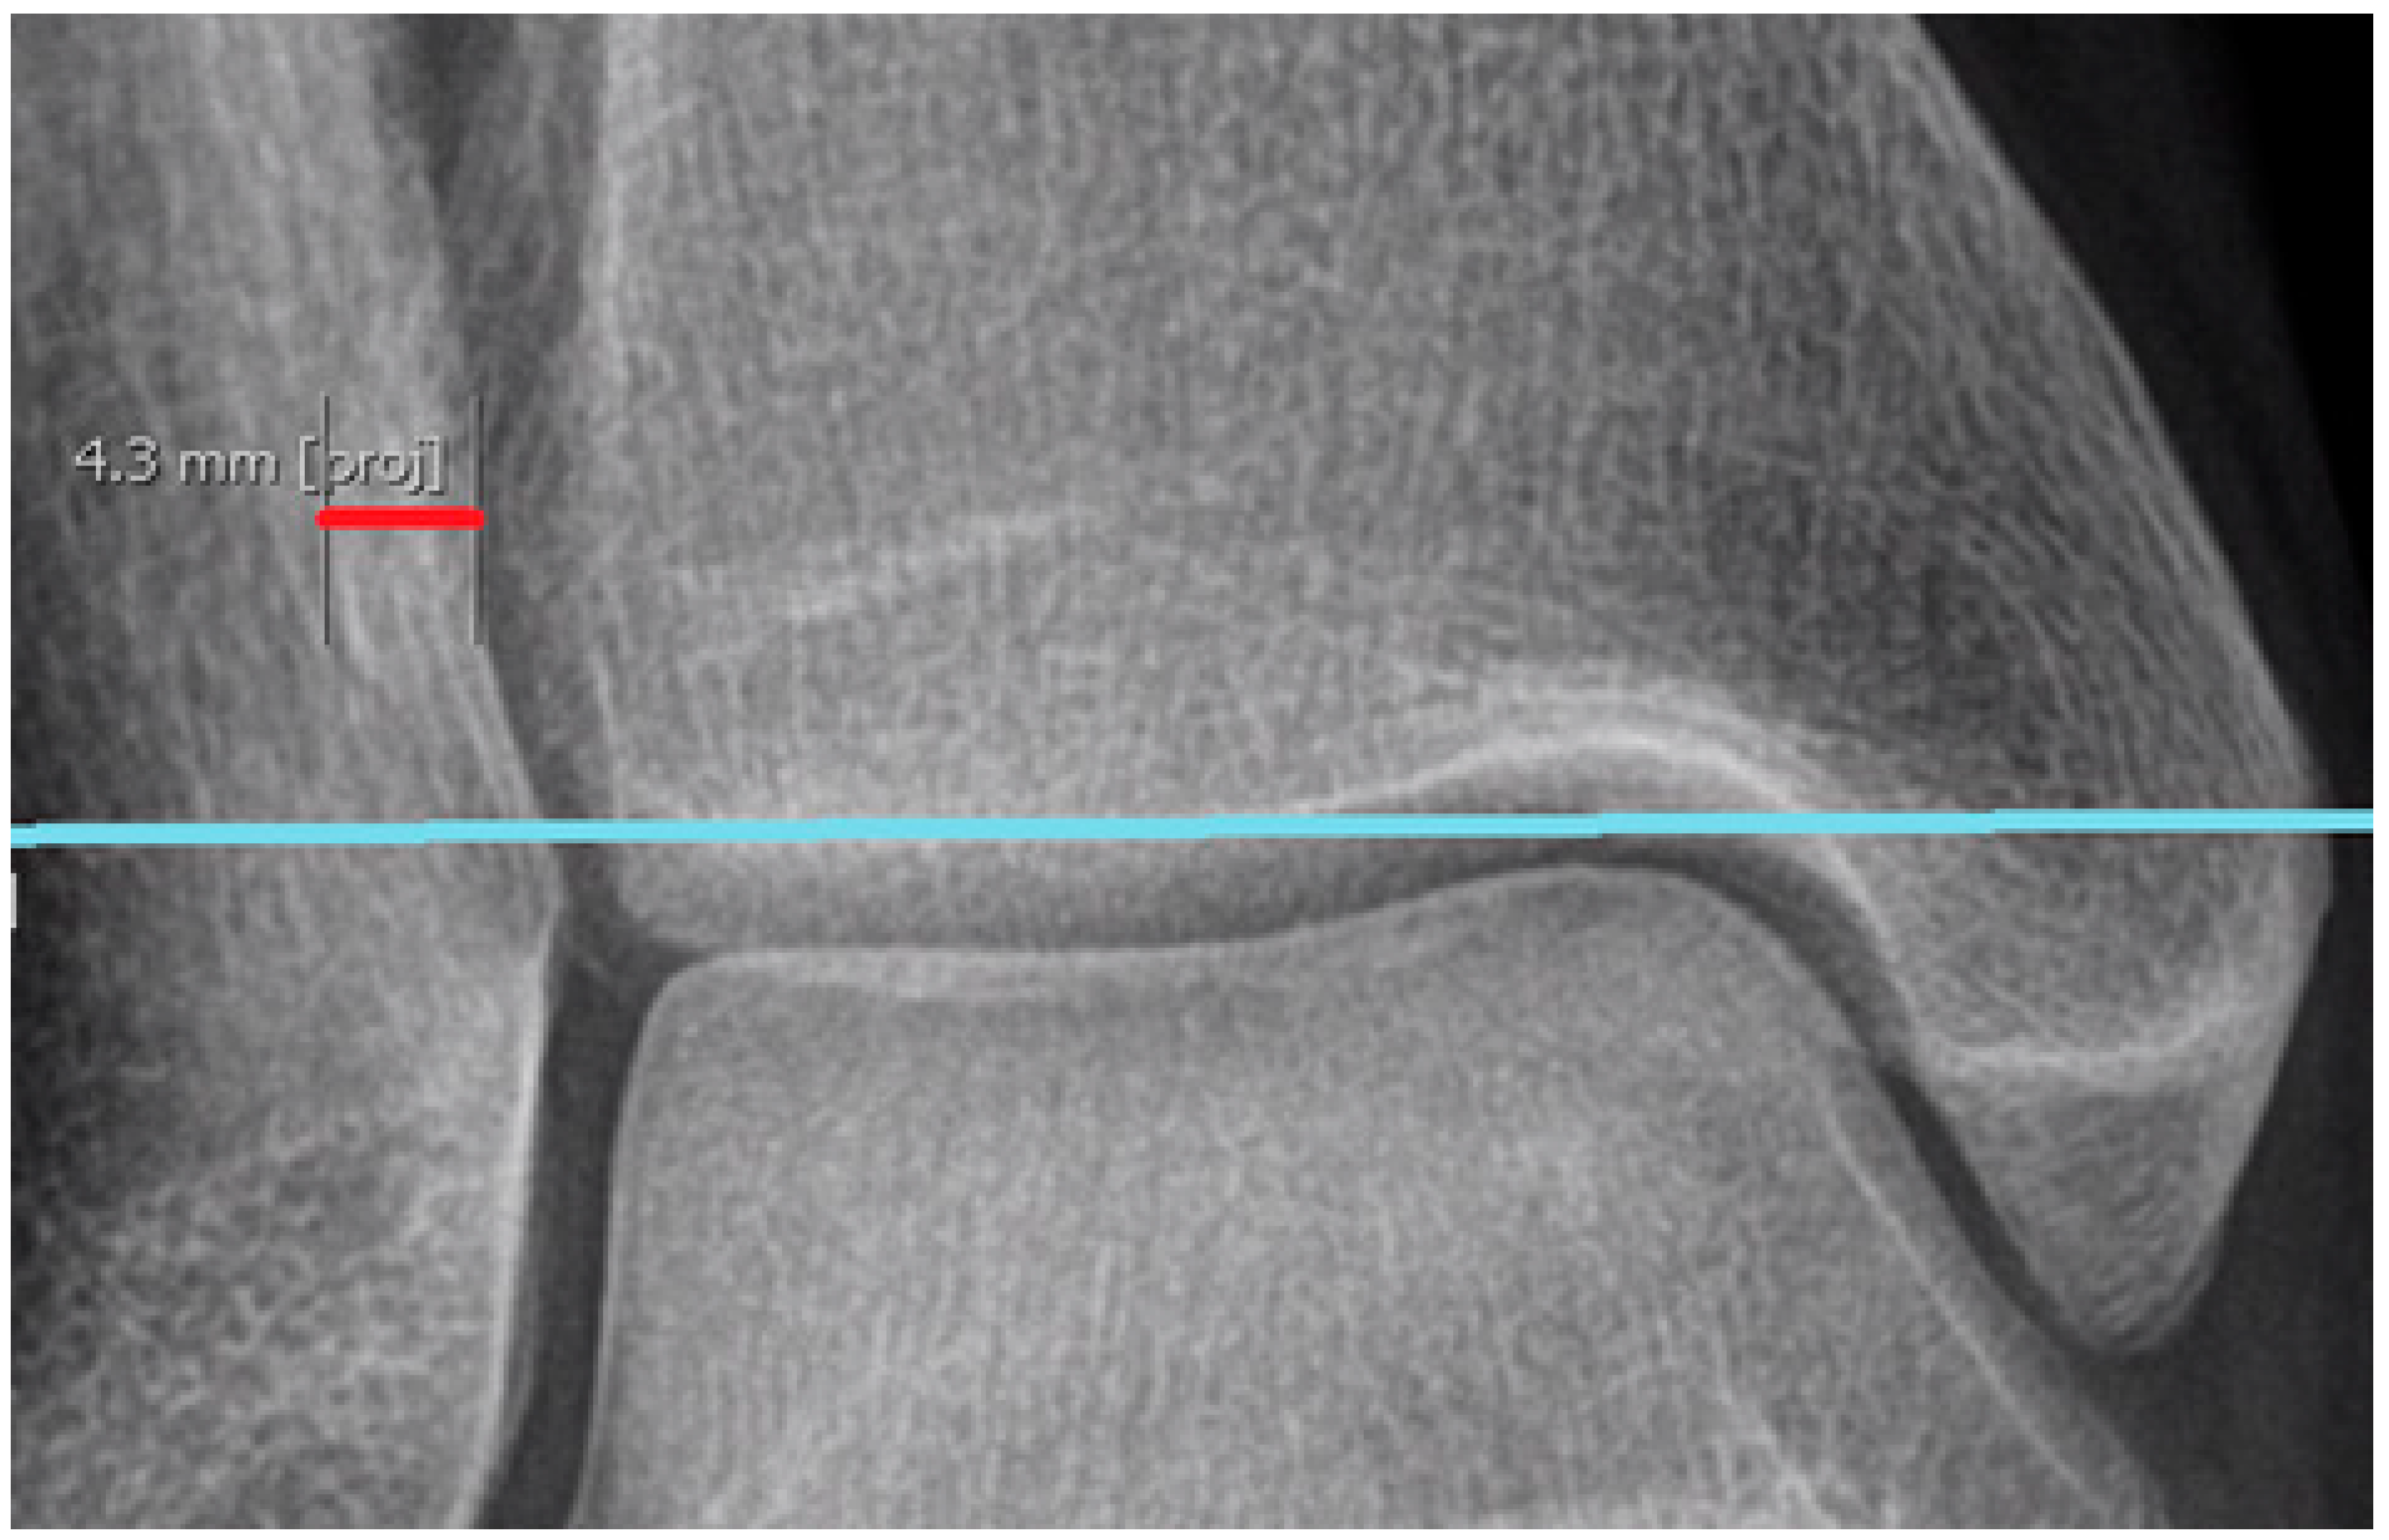

First, a transverse line was positioned in the coronal plane to symmetrically intersect the lateral marginal point of the tibial plafonds in both ankles (Figure 1).

Adjusted in this manner, the line enables us to measure both ankles with a single cut. Based on our experience, this approach reduces the time required for measurements and improves the agreement between observers. Therefore, it has become our preferred method instead of adjusting separate planes for each ankle.

Second, the levels for further calculations were distinguished by perpendicularly measuring the distances proximal and distal to the transverse line. For parameters 1, 2, 3, and 4, measurements were conducted separately at various levels: 7, 8, and 9 mm proximal to the lateral margin of the tibial plafond; for parameter 5, measurements were taken at 5, 6, and 7 mm distal from the lateral margin of the tibial plafond (Figure 1).

Figure 1. The transverse line (marked in red) is adjusted to intersect both ankles at equivalent levels, utilizing the lateral margins of the tibial plafonds as references. The green line represents the sagittal plane, which is irrelevant to the adjustment process. The two measurement lines visible in the figure (light-blue and orange lines) extend distally from the transverse line (red), indicating the lowest and highest levels for further measurements: 5 mm for the light-blue line and 7 mm for the orange line. Other levels of measurement are not marked in the figure.